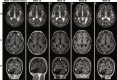

Case presentation: The patient was admitted to the hospital due to psychosis, speech impairment, and behavioral changes over the last three months. She had previously been healthy, except for a cerebellar stroke secondary to paroxysmal atrial fibrillation. Magnetic resonance imaging (MRI) revealed multiple contrast-enhancing white matter lesions suspicious of cancer metastases. Due to suspicion of edema, dexamethasone was administered, and the patient was released while waiting for a stereotactic brain biopsy. Eight days later, she suffered tonic seizures and was readmitted. Intravenous levetiracetam gave rapid effect, but the patient was paranoid and non-cooperative, and dexamethasone was unintentionally discontinued. Ten days later, the brain biopsy revealed demyelination, abundant perivascular T cells, macrophages, and scattered JCPyV-infected oligodendrocytes, rendering the diagnosis of PML-IRIS. The cerebrospinal fluid contained low amounts of JCPyV-DNA, and plasma contained high levels of anti-JCPyV immunoglobulin G. Despite extensive immunological testing, no evidence of immunodeficiency was found. The patient gradually recovered clinically and radiologically. More than 19 months after diagnosis, the patient has only a slight impairment in language and behavior.

Conclusions: An apparently immunocompetent elderly person developed clinically symptomatic PML, which spontaneously resolved with symptoms and signs of IRIS. The atypical MRI lesions with contrast enhancement and the lack of known immunological risk factors for PML delayed the diagnosis, eventually proved by biopsy. PML and PML-IRIS should be considered in the differential diagnosis of patients presenting CNS symptoms and focal lesions with contrast enhancement on MRI.